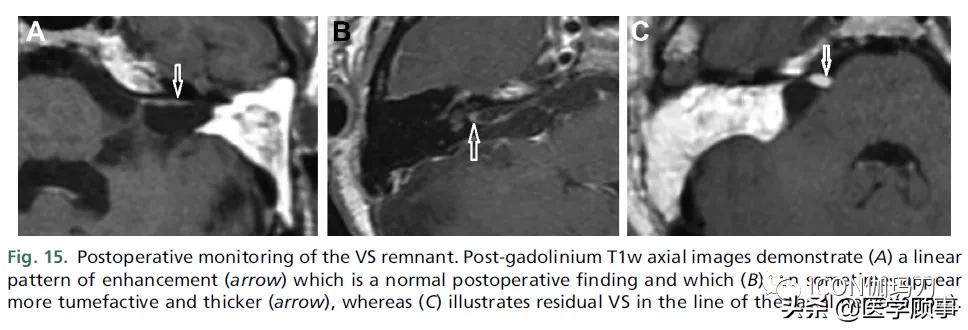

虽然可以实现肿瘤全切除(GTR),但手术的目标已从全切除转向功能保留。近全切除(NTR)残留小于5%,次全切除(STR)残留大于5%。在GTR的背景下,由于炎症和早期纤维化,切除部位仍然预期有强化。在术后1年,可以根据线性增强的模式对复发风险进行分层(3%会出现),但很少进展,而结节性强化的复发率可增加6 - 16倍。目前还没有标准化的GTR的监测方法,但稳定的MRI改变一般需要随访3 - 5年,取决于是否有线性或结节性强化。在这种情况下,随访MRI是否需要钆剂增强是有争议的。在近全切除(NTR)和次全切除(STR)的情况下,肿瘤残余通常与面神经有关(图15)。NTR和STR的MRI监测方案与术前肿瘤类似;然而,小的肿瘤残余显示出更惰性的生物学行为。

图15。VS残留术后监测。钆剂后T1w轴位片显示(A)线性强化(箭头),这是正常的术后表现,(B)有时会出现更大和更厚的肿起(箭头),(C)显示面神经线上残留的VS(箭头)。